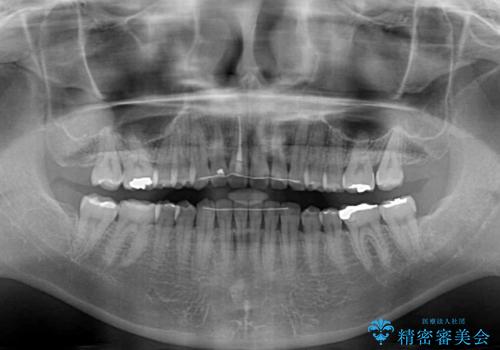

- 前歯の隙間を気にして来院された患者様です。

隙間、捻転ともに軽微でありましたが、下顎前歯の突き上げにより隙間ができていたため、インビザラインを用いて咬み合わせを改善しながら前歯の歯列を整えていくこととしました。

当初は1年程度で終えられると思いましたが、治療途中から装着時間が短くなったり、来院間隔が長期になったりとし、結果として4年半以上の治療期間となりました。

治療途中に上顎前歯は失活してしまいましたが、変色が顕著ではないため、経過を見ていくこととなりました。